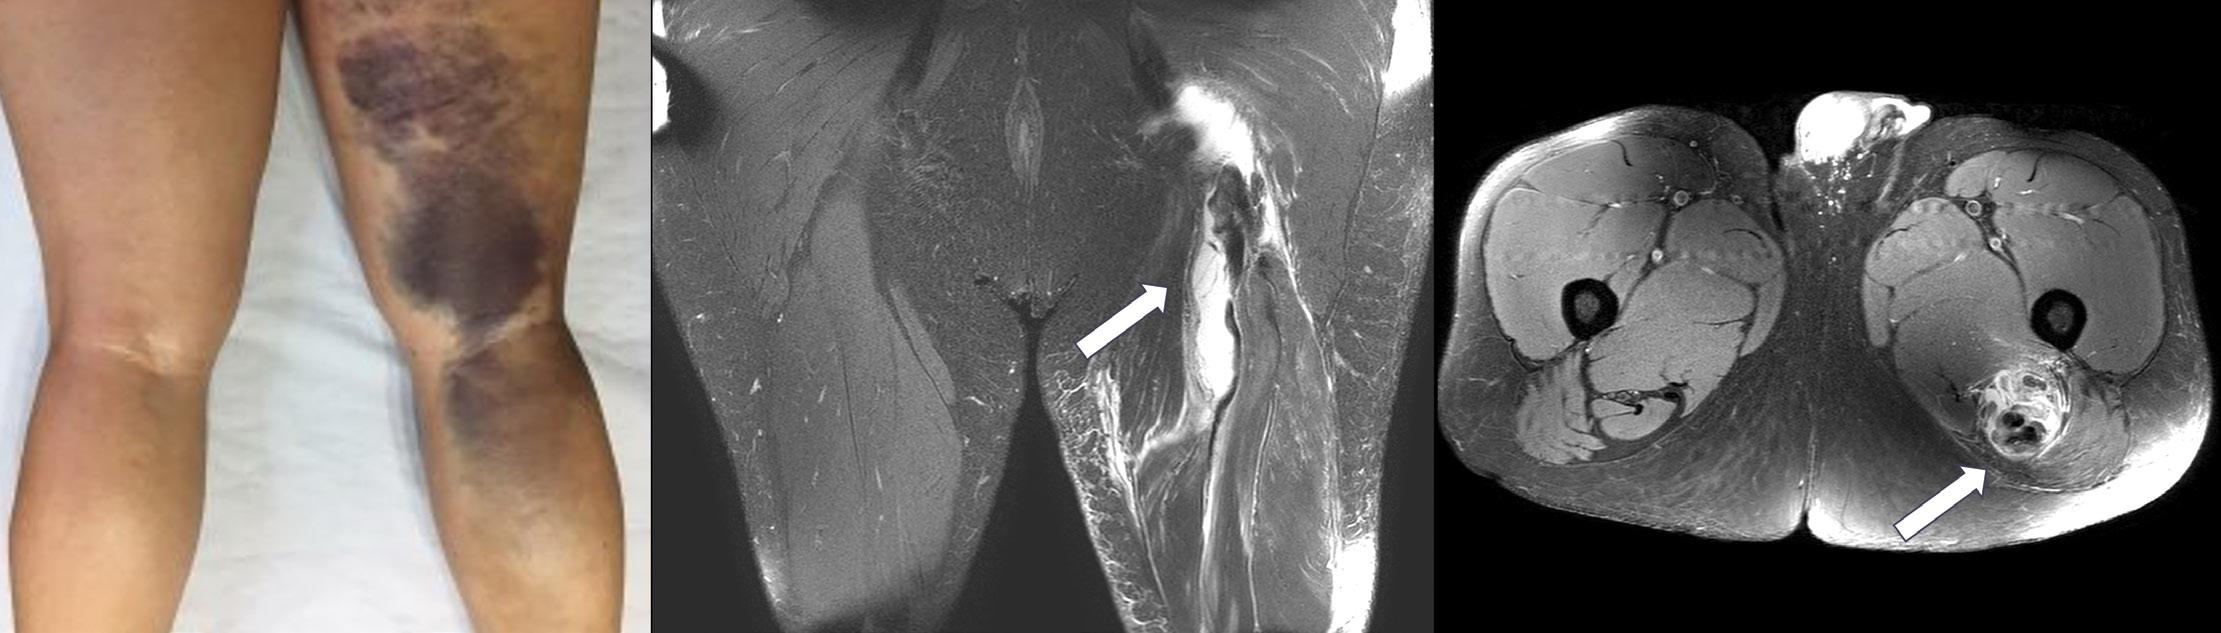

Clinically, patient presentation following injury can also be varied. Often patients may report a sharp pain at time of injury located around the buttock or posterior thigh, which may also be accompanied by an audible crack or pop. Immediate weight-bearing ability may be compromised, while sitting

(due to compression over the injury site), postures/movements that require increased hip flexion (such as putting on shoes and socks) and activities that require hamstring activation (such as squatting and stair ascent) can be challenging. Bruising and swelling can often be encountered given the traumatic nature of such injuries. Nonetheless, regardless of the injury mechanism, the end result can be painful and functionally limiting, with a persistent and significant level of disability if missed or misdiagnosed.